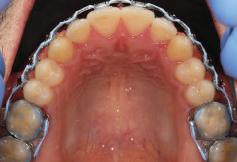

7Dental Tribune Bulgarian Edition / октомври 2022 г. Преди лечението Фиг. 1 Фиг. 4 Фиг. 7 Фиг. 10 Фиг. 13 Фиг. 16 Фиг. 17 Фиг. 18 Фиг. 19 Фиг. 20 Фиг. 11 Фиг. 14 Фиг. 12 Фиг. 15 Фиг. 8 Фиг. 9 Фиг. 5 Фиг. 6 Фиг. 2 Фиг. 3

8 Dental Tribune Bulgarian Edition / октомври 2022 г. По време на лечението Фиг. 21 Фиг. 25 Фиг. 30 Фиг. 31 Фиг. 34 Фиг. 38 Фиг. 40 Фиг. 44 Фиг. 48 Фиг. 50 Фиг. 49 Фиг. 46 Фиг. 39 Фиг. 41 Фиг. 45 Фиг. 47 Фиг. 42 Фиг. 43 Фиг. 35 Фиг. 36 Фиг. 37 Фиг. 32 Фиг. 33 Фиг. 26 Фиг. 28 Фиг. 29 Фиг. 27 Фиг. 22 Фиг. 23 Фиг. 24

9Dental Tribune Bulgarian Edition / октомври 2022 г. След лечението За авторите: Д-р Манол Ивчев е създател на COLDY DENT Functional Atelier, завършва дентална медицина във ФДМ, София. Шест години е стажант в ортодонтска практика. Интересите му са изцяло насочени към функционалната дентална медицина. Посещава курсовете на Доусън и Льо Гал. Преминава редица обучения, акредитирани от Института на Славичек във Виена – VieSID. Впоследствие става най-младият инструктор във VieSID. Придобива права да преподава философията на проф. Рудолф Славичек в България. В практиката си се придържа към протоколите на Славичек за функционално лече ние и диагностика, тъй като те са насочени към комплексно лечение. Завършва всички нива за морфология на зъбите и моделаж при Janos Mako. Повишава знанията си по функционална ортодонтия чрез индивидуален курс в Румъния. Д-р Ивчев е и сертифициран зъболекар по лингвална ортодонтия от Катедрата по ортодонтия от Университета по стоматология в Тегу, Южна Корея. Сертифициран е и за лечение на ортодонтски аномалии чрез миофункционални апарати, а също и за ортодонтия, подпомагана от миниимпланти, отново от Университета по стоматология в Южна Корея. Завършва индивидуално обучение по функционална ортодонтия в Университета по дентална медицина в Богота, Колумбия, както и индивидуално обучение по функционална ортодонтия и физиотерапия по про токола на Mariano Rocabado. Има завършено индивидуално обучение по функционална зъботехника и функционален Wax-Up клас I,II и III. Завършва курс за Digital Smile Design и Skin Concept в Люксембург при Christian Coachman, Florin Cofar, Paulo Kano, Josef Kunkela, Livio Yoshinagа. Зт. Leandro Gambogi, Бразилия, завършва зъботехника през 1999 г. Експерт и пионер в дигиталната диагностика. Лектор и инструктор на курсове в областта на дигиталното протезиране. Понастоящем е главен изпълнителен директор и зъботехник в DENTALE DIGITAL LAB. В периода януари 2005 г. – декември 2006 г. завършва бизнес управление и администрация в Methodist University Center Izabela Hendrix. Съавтор на книгата Odontologia Digital: Desafiando os Limites, глава 5: „Дигитално включване във времето. Технология CAD/CAM“. Преминал множество обучения при световноизвестни кли ницисти. Фиг. 51 Фиг. 54 Фиг. 57 Фиг. 58 Фиг. 63 Фиг. 64 Фиг. 65 Фиг. 59 Фиг. 61 Фиг. 62 Фиг. 60 Фиг. 55 Фиг. 56 Фиг. 52 Фиг. 53 Фиг. 66